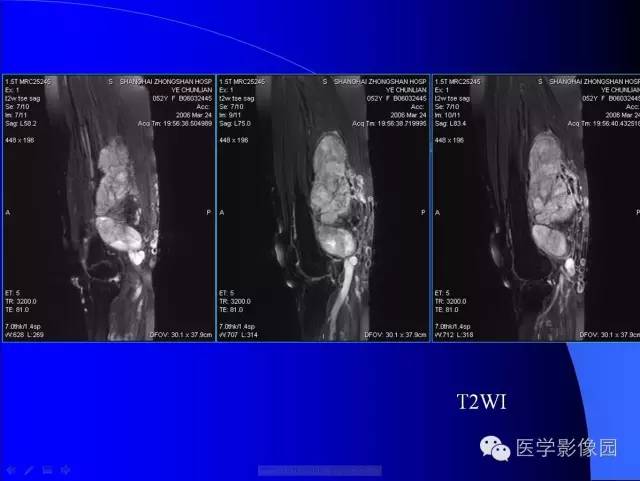

【病例】大腿恶性孤立性纤维瘤1例MR

病史:女,52岁,左大腿包块30年,逐渐长大。

孤立性纤维瘤起源于弥漫分布于人体结缔组织中CD34阳性的树突状间叶细胞。多见于头颈部、上呼吸道、腹腔和周围软组织。发病高峰40~ 60 岁, 女性多见。临床上多数病例表现为局部缓慢生长的无痛性包块。随着包块的增大, 会出现相应部位的压迫症状。孤立性纤维瘤多数病例临床上呈良性经过, 约10% 的非典型性和恶性孤立性纤维瘤局部复发率或远处转移率较高(80% )。